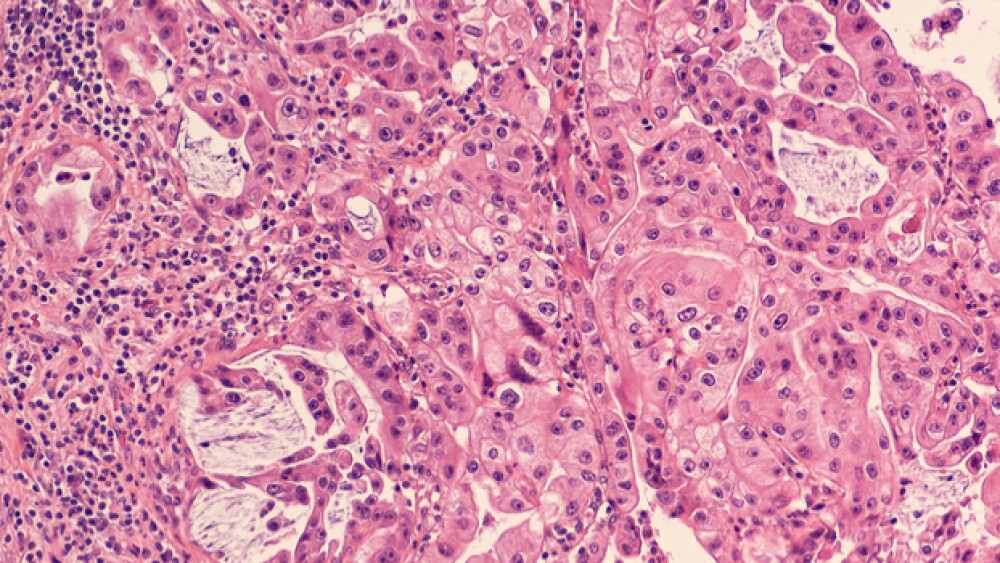

Locally advanced pancreatic cancer is a type that has grown into major blood vessels and as a result, can’t be removed safety via surgery (unresectable). The cancer has not yet metastasized outside the pancreas.

The new aspect of the procedure and the study is the addition of losartan, a drug for high blood pressure that is marketed as a generic form and under the brand name of Cozaar. Earlier studies by co-author Rakesh K. Jain, director of the Steele Laboratories for Tumor Biology at MGH and Andrew Werk Cook Professor of Radiation Oncology at Harvard Medical School, found that the drug improved chemotherapy delivery in animal models of breast, pancreatic and ovarian cancer. Its method of action for this is to relieve pressure in the tumor microenvironment that actually blocks drug delivery and decreases the oxygen supply, which is necessary for the tumor-killing activity of radiation therapy. Jain’s studies also indicated that cancer patients who were otherwise taking losartan or similar hypertension medications generally lived longer than others receiving the same types of cancer therapies.

After this stage, 34 of the 49 patients had improved to where they could have their cancers removed. Thirty of the 34 patients’ cancers were successfully removed eliminating all evidence of cancer. For three patients, a pathologic complete response was observed, meaning no tumor was observed anywhere.